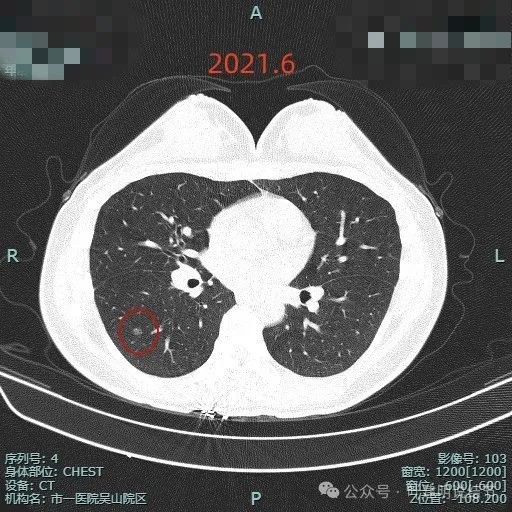

肺磨玻璃结节术后病理是不典型增生,这刀白开了吗?

病史摘要:患者主因“检查发现肺部阴影5年”就诊。5年前当地医院体检胸部CT提示肺部结节,无明显症状未治疗。2024年11月杭州市肿瘤医院复查胸部CT,右肺多枚小结节,LUNG-RADS 2,建议年度随诊。现患者无不适,为求进一步诊治入院。起病以来,患者神志清,精神、胃纳、睡眠、二便正常,体重无明显变化。诊疗过程:体格检查未提及。多次胸部CT显示右下叶磨玻璃结节,轮廓与瘤肺边界清楚,

肺不典型增生